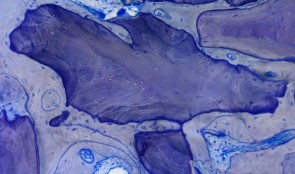

Analytical Methods: Histology

based on the book chapter by Dieter D. Bosshardt Summary Histological assessment, which can be quantitative or qualitative, is an indispensable tool for investigation of soft tissue regeneration. Harvesting tissues raises ethical considerations, but less invasive forms of evaluation, such as clinical measures and imaging, only complement the descriptive analysis, rather than replace it, by showing how cells respond to biomaterials in vivo. This chapter explores various methods for evaluating hard and soft oral tissues, such as histomorphometry, in situ hybridization and autoradiography, in the context of procedures like socket preservation, ridge augmentation and sinus floor elevation. As well as outlining suitable endpoints and landmarks, it discusses tools and techniques for taking biopsies, cutting, sectioning and embedding samples, and the use of microscopy and illumination. The authors address the challenges posed by different biomaterials -- not all can be sectioned, and some react with the chemicals used for processing samples. Thus tissue sections may be of unpredictable quality and be affected by artifacts introduced before fixation (if the tissue gets crushed during harvesting or contaminated by oral pathogens) or during fixation or preserving. Other challenges include the acquisition, processing, analysis and storage of digital images, and the huge variations in analytical equipment and methods used in different laboratories, where the need to apply laboratory standards and minimize examiner variation is emphasized. Open full-text PDF (1.9 MB) -